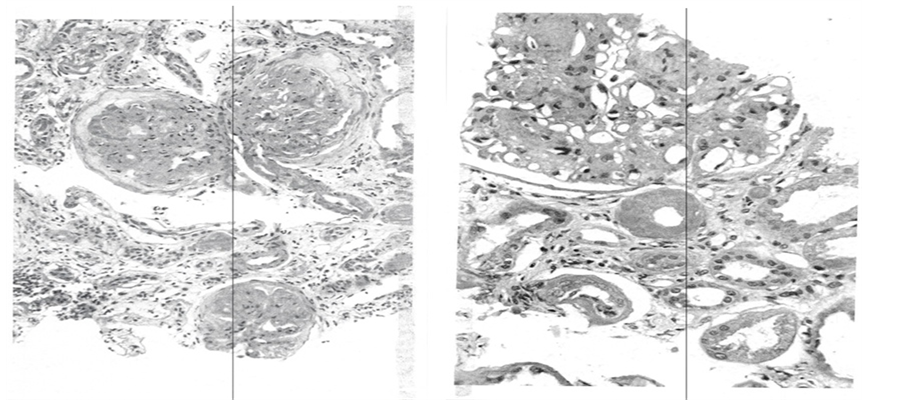

A 54 years white male truck driver has had two hospital admissions in a period of two months. He went to urgent care clinic in December 2013 for routine physical exam and was told that he had very low kidney function and sent to hospital for investigation. He gave history of diabetes for 20 years and was treated with metformin and glyburide. He was not advised to take insulin. He was also taking a combination of Lisinopril (ACEI) and hydrochlorothiazide (HCTZ), for hypertension control. Upon hospital admission his BP was 182/85 mmHg. A basic metabolic panel showed glucose of 94 mg/dL. (5.2 mmol/L), BUN 65 mg/dl, serum creatinine 4.5 mg/dl with eGFR 15 ml/min. His hemoglobin was 10.8 g/dL. 24 hour proteinuria was 9962 mg (almost 10 g). Percutaneous kidney biopsy was done. He tolerated the procedure well and had no post biopsy bleeding. Lisinopril, HCTZ, metformin and glyburide were discontinued and started on aspart insulin (Novolog®) and amlodipine (Norvasc®) for glucose and BP control, respectively. He was discharged from the hospital and followed in author’s office. Kidney biopsy showed advanced diabetic glomerulopathy on the right and severe tubulointerstial changes on the left (Figure 4).

Figure 4. Biopsy results. Left: Three glomeruli are sclerozed; Right: Nodular diabetic glomerulosclerosis Marked. A periglomerular arteriole with hyalinosis is noted. Atrophic tubules are seen.